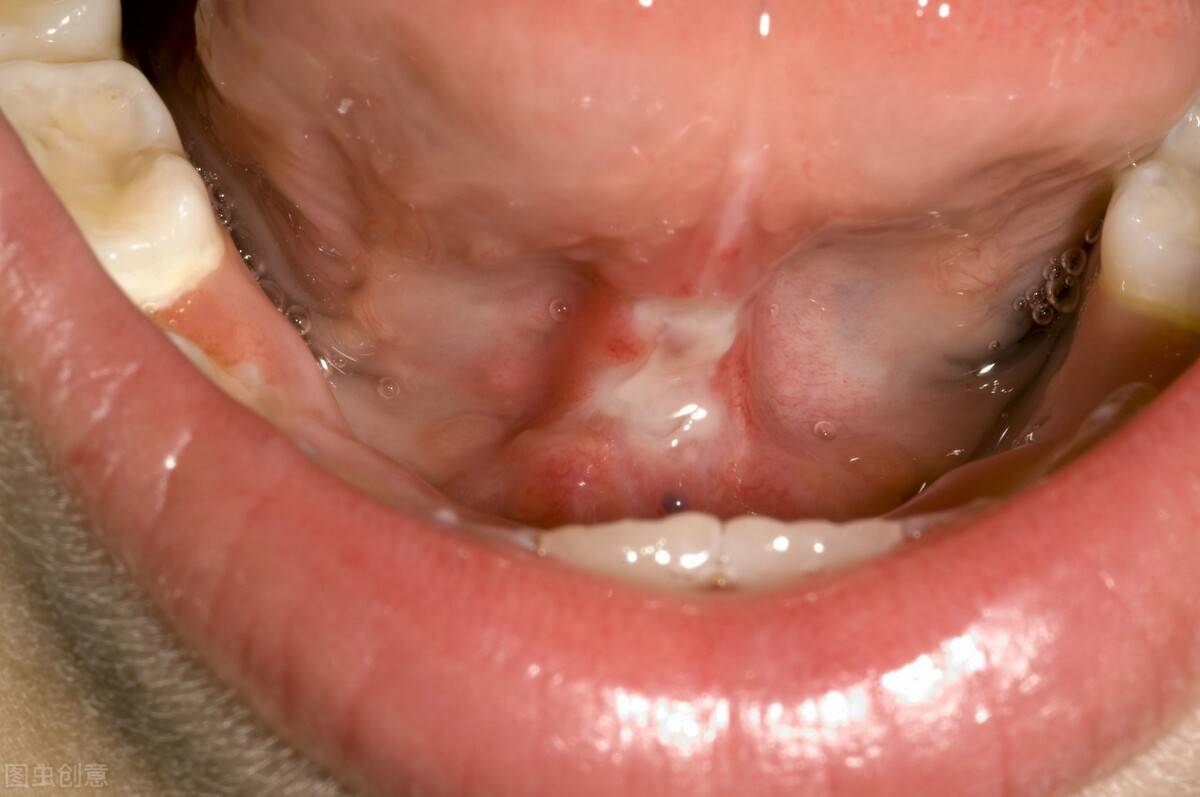

⊙▽⊙ 小孩说话不利索?多个角度揭秘“模糊语言”真相当发现小孩说话不清楚时,家长们难免心生担忧。小孩说话不清楚并非单一因素所致,其背后涉及生理、心理、环境等多方面因素。接下来,我们将从多个维度深入剖析,探寻导致小孩说话不清楚的原因。 一、生理因素的影响 1.口腔结构与功能异常 若小孩存在舌系带过短的情况,舌头的活动...

ˋ△ˊ 孩子不会说话、说话晚的8个常见误区,别让你的误解耽误了孩子成长!今天给大家讲讲;关于孩子不会说话、说话晚的8个常见误区,别让你的误解耽误了孩子成长! 关于儿童语言发育的几个常见误区及正确认知 误区一:舌系带短,剪了就能说话? 事实:舌系带的长度与儿童是否说话无直接关联。舌系带过短可能影响部分音节的发音清晰度,如舌尖后音和舌尖中音...